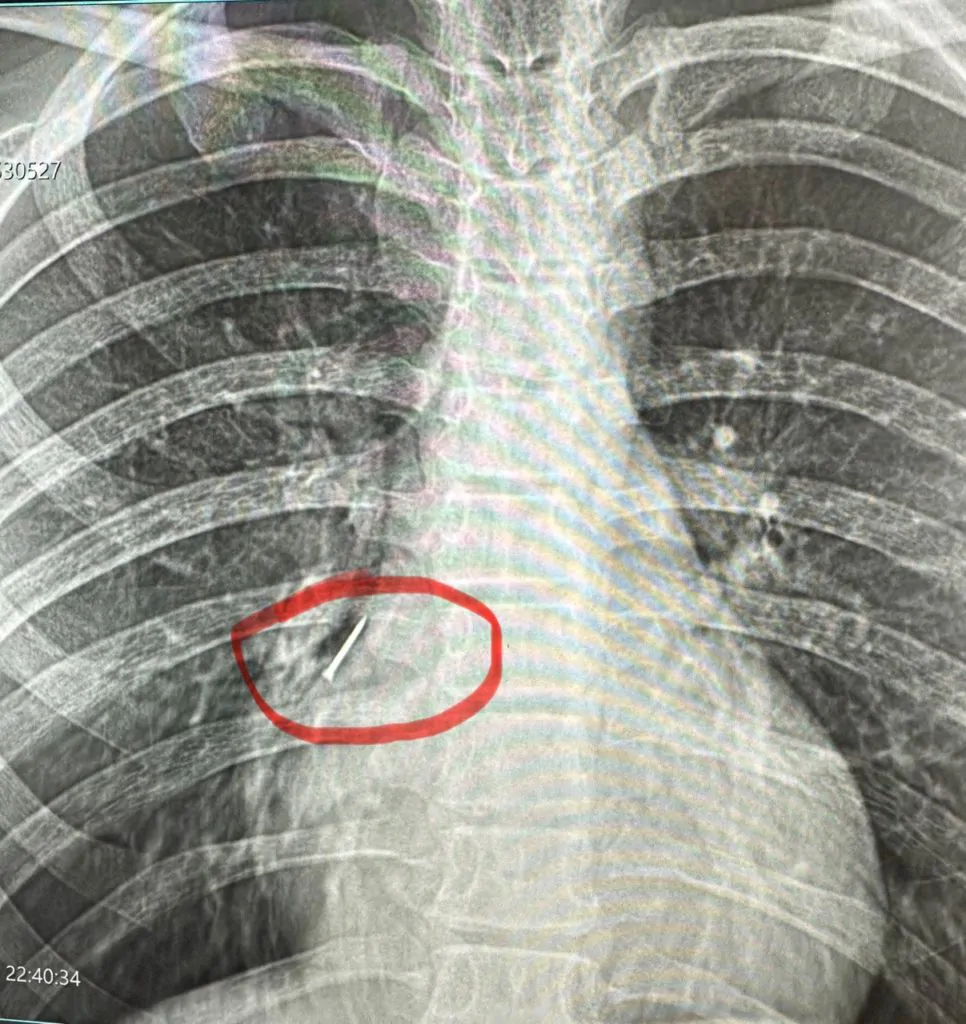

Після додаткових обстежень, зокрема рентгенографії, з’ясувалося, що у кишківнику дитини сторонні тіла».

Під час операції лікарі виявили магніти, два з яких склеїлись між собою у різних відділах кишківника. В місці з’єднання утворився пролежень, а згодом — перфорація, внаслідок чого кишковий вміст витік у черевну порожнину.

«Непросто було видалити й магніти. Їх довелося «завести» в апендикс і видалити разом із ним. Дівчинку виписали додому на 10-й день після оперативного втручання», — Василь Демчук.